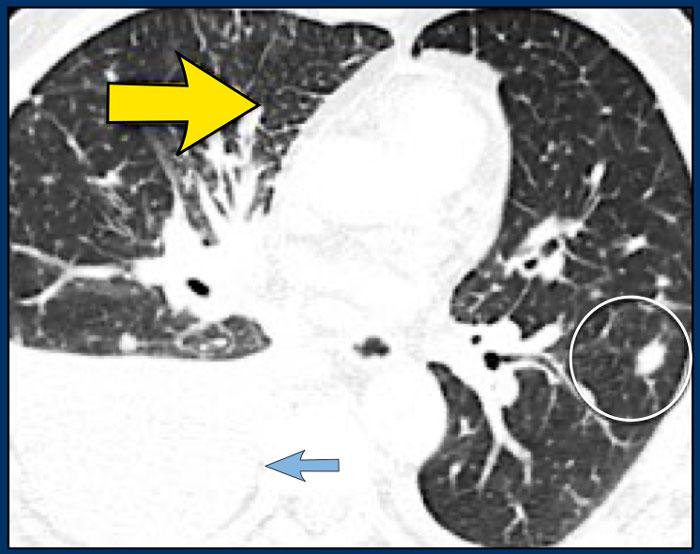

Bệnh nhân khác với Ung thư hạch bạch huyết lan tỏa có dày vách liên tiểu thùy (mũi tên vàng).

Kèm theo tràn dịch màng phổi (mũi tên xanh) và tổn thương di căn phổi (vòng tròn).